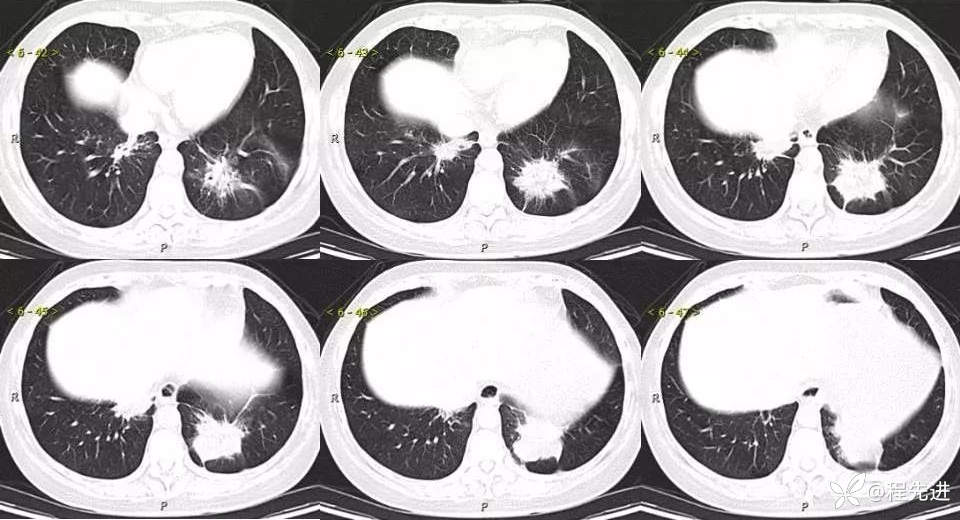

主诉:体检发现肺结节2周

现病史:患者2周前体检时发现两肺多发高密度影。无咳嗽、咳痰,无咯血、呼吸困难,无胸闷、胸痛,无发热、潮热盗汗。